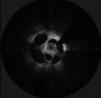

A 67-year-old man with ischemic heart disease and severely reduced ejection fraction underwent coronary angiography for a non-ST-elevation myocardial infarction. Angiography revealed a lesion in the proximal left anterior descending (LAD) artery (Video 1). The angiographic appearance of the lesion did not unequivocally identify its nature, the possibilities being a complex dissection or a recanalized thrombus. Optical coherence tomography (OCT) was therefore performed (Figure 1 and Video 2). The unusual image obtained confirmed the presence of multiple lumens in the LAD, apparently following recanalization of a thrombus. Angioplasty of the LAD was accordingly performed and a drug-eluting stent was placed, with an excellent final result (Videos 3 and 4).

Thrombus recanalization can sometimes give rise to angiographic images of considerable complexity, suggesting etiologies that pose greater technical challenges, such as complex dissections. Intracoronary imaging methods such as OCT can clarify the nature of such lesions and enable appropriate treatment, avoiding technically more complex approaches that could potentially have iatrogenic consequences.